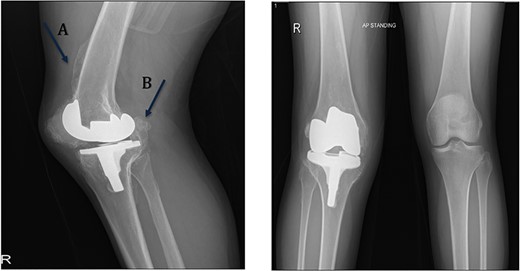

A 32-year-old female known case of rheumatoid arthritis affecting both knees presented to our clinic complaining of severe right knee stiffness post TKA 4-years-ago done in an outside facility (Figs. 1 and 2). She lives in a rural community and was on hydroxychloroquine, but her disease was active as she was not compliant to her medication. On physical examinations, the right knee was larger in size compared to the left knee without joint effusion. Range of motion was zero on flexion, −10° in extension. Standing knee X-ray showed HO around the prosthesis (Fig. 2). Computed tomography (CT) demonstrated extensive HO with implants fixed in place (Fig. 3). Revision surgery and replacement of the prostheses was considered to restore function.

Preoperative standing X-ray showing heterotopic ossification around the prosthesis with preserved knee joint. (A) Heterotopic bone extending proximally on the anterior surface of the femur. (B) Posterior heterotopic bone fusing the knee joint. Careful removal with osteotomes and bone curettes was necessary to remove the old implants.

The old medial parapatellar approach was utilized. The medial and lateral gutters were completely released up to the posteromedial corner. When the knee was too stiff to be mobilized further, the patellar tendon was found to be severely contracted and shortened with patella baja deformity. A tibial tubercle osteotomy was needed for adequate exposure. Osteotomy fragment measured 6 cm with 1.5 cm thickness, after which we became able to flex the knee. The components were completely engulfed by capsular heterotopic bone (Fig. 2). Using osteotomes and burrs, the tibial and the femoral components were slowly visualized. Both components were found to be well fixed. Carful removal of the posterior heterotopic bone was done with a bone curette, which finally allowed for component removal. Intraoperative culture samples were taken as routine measure for revision surgeries. RT-Plus modular rotating hinge knee system (Smith & Nephew, Memphis, TN, USA) was used. The procedure was started with reaming the tibia up to size 12 mm. It was sized to be size four. Proximal drilling and rasping were done, and posterior offset stem was used.